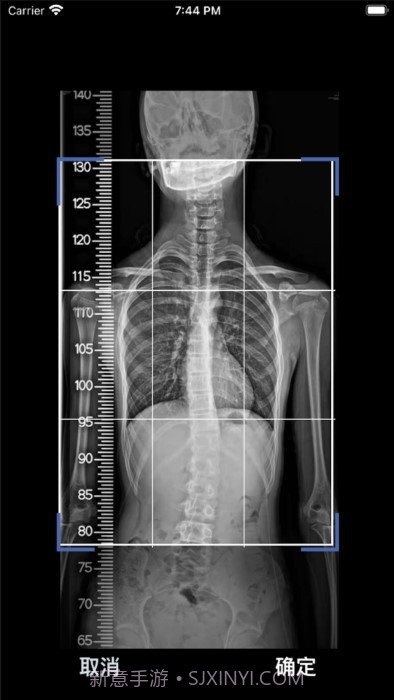

这款cobb角测量分析平台简直是医生和脊柱侧弯患者的福音!🌟 通过智能测量功能,能够迅速获取cobb角,准确率高得让人放心。对于有脊柱健康需求的小伙伴们来说,了解自己的状况特别重要,不仅能省时省力,更能随时存储和导出数据,后续分析也是轻松搞定!总之,这款应用为提高医疗效率、帮助患者掌握健康状况提供了强有力的支持,真心推荐给大家!

智能测量功能超赞,帮你快速获取cobb角,省时省力!

自动识别和标记椎骨,精准度高达95%,真是放心!